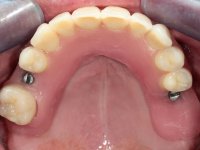

In every clinical step, the healing abutments were polished in order to maintain healthy peri-implant tissues.

The bars were finally screwed over the implants with the adequate torque and the overdentures set-in-place. Maintenance instructions were given to the patient regarding oral hygiene and overdentures insertion / removal.